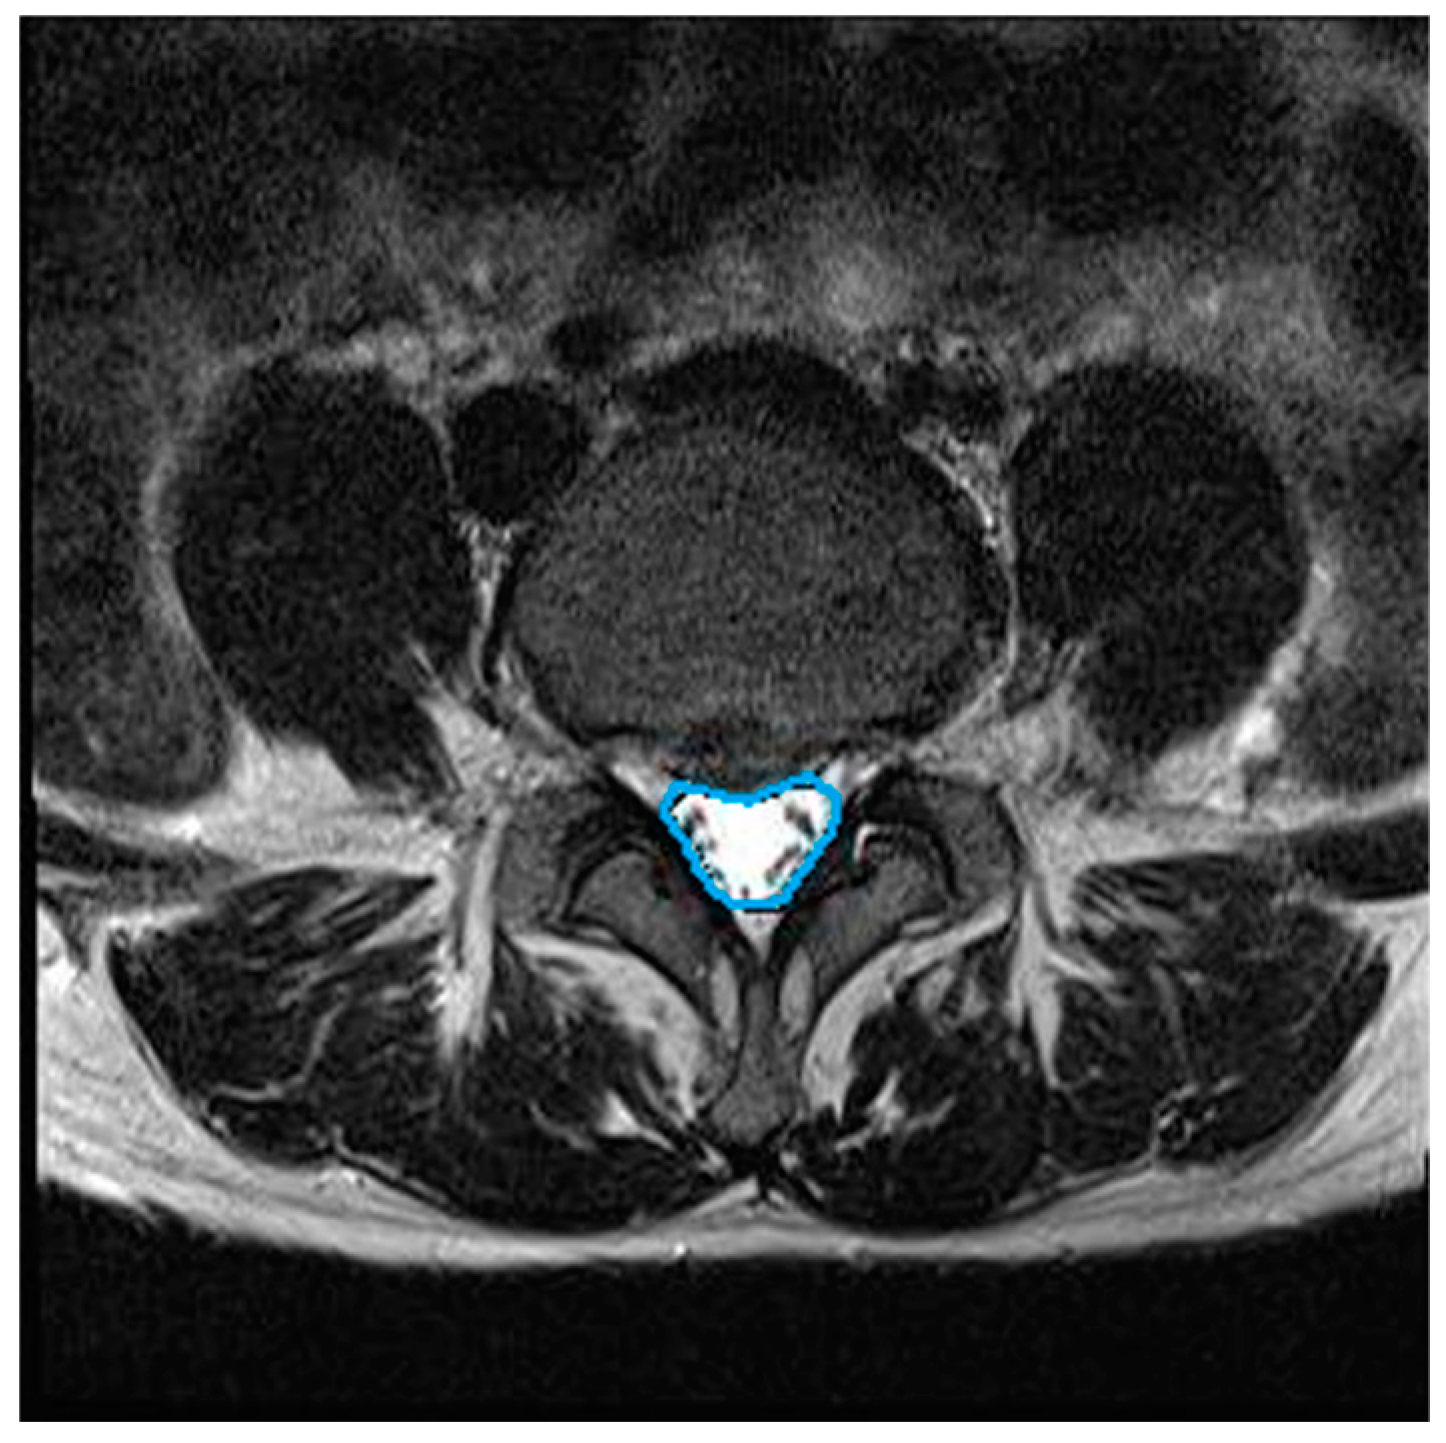

We assessed the changes in the lumbar central canal area before and after lumbar traction. All MRI examinations were performed using a 3 Tesla MRI (Siemens Healthcare GmbH, Erlangen, Germany). Using T2-weighted images (field of view (FOV): 150 × 150 mm; echo time (TE): 108 ms; repetition time (TR): 4500 ms), the axial image of the disc level associated with the greatest neurological compression was selected for measurement. In this study, the L4/5 or L5/S1 intervertebral disc level was selected. Digital measurement of the central canal area outline was performed by tracing the dural cross-sectional area boundaries on the axial MRI at the disc level (Figure 2). Measurements were conducted by a single-blinded musculoskeletal radiologist with more than 10 years of experience, using a previously described method [22]. Each measurement was repeated three times by the same musculoskeletal radiologist to enhance repeatability. The intra-observer intra-class correlation coefficient (ICC) reliability was high (>0.8, 95% CI).

Figure 2.

Central canal area in axial view of lumbar spine MRI (Magnetic Resonance Imaging).